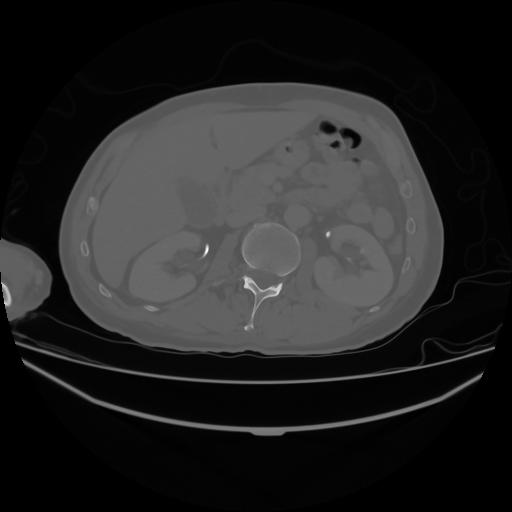

4 CUERPO,CE,Axial,3.0,CUERPO,,